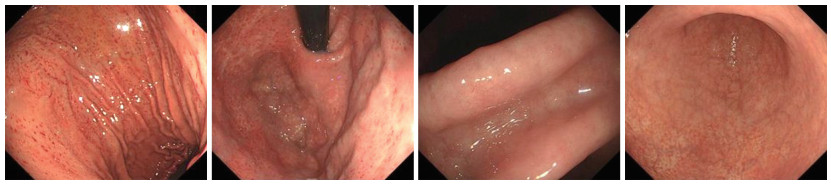

幽门螺旋杆菌感染相关胃炎与自身免疫性胃炎患者病情特征及其鉴别诊断因素分析

华男, 方莹, 严丽园, 陈盼云, 鲁姗姗, 周建波

2026, 24(2): 225-230. doi: 10.16766/j.cnki.issn.1674-4152.004366

9 0

摘要:

目的  分析幽门螺旋杆菌感染相关胃炎与自身免疫性胃炎(AIG)患者病情特征,并探究影响鉴别诊断的因素,为早期识别胃炎类型提供理论依据。  方法  选取2022年9月—2023年12月于宁波大学附属阳明医院治疗的49例幽门螺旋杆菌(Hp)感染相关性胃炎患者为Hp组,选取同期49例自身免疫性胃炎患者为AIG组。收集2组患者的临床资料,并对患者病情特征和鉴别诊断因素进行回顾性分析及总结。  结果  2组患者胃轻瘫主要症状指数(GCSI)、抗内因子抗体(IFA)阳性、胃蛋白酶原Ⅰ(PGⅠ)、胃蛋白酶原Ⅱ(PGⅡ)、PGⅠ/PGⅡ值、胃泌素-17(G-17)比较,差异均有统计学意义(P < 0.05)。Hp相关性胃炎胃镜下可见胃窦黏膜红白相间,以白为主,黏膜下血管透见。AIG胃镜下可见胃底、胃体黏膜变薄,红白相间,以白为主,黏膜下血管透见,可见增生性息肉,而胃窦部相对正常。Hp相关性胃炎组织病理学表现为固有层浅表单核炎性细胞和胃腺颈部中性粒细胞的弥漫性浸润,可见肠型上皮细胞取代泌酸腺黏膜中的上皮细胞。AIG组织病理学表现为固有层中基底层为主的慢性炎性细胞浸润,可见腺上皮的假幽门化生或胰腺腺泡细胞化生。多因素logistic分析显示,PGⅠ/PGⅡ值(OR=0.278,P < 0.001)、G-17(OR=1.268,P=0.005)均为影响Hp相关性胃炎与AIG鉴别诊断的因素。  结论  G-17、PGⅠ/PGⅡ值和组织病理学可用于鉴别Hp相关性胃炎和AIG,以提高诊断的准确性。